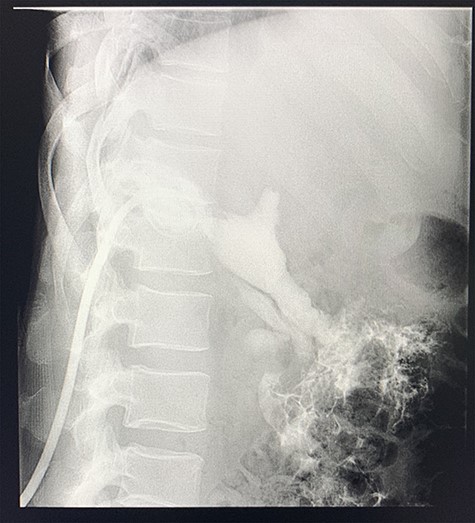

Sinogram obtained by anterioposterior x-ray of segment of lower chest/abdomen following injection of contrast into the percutaneous pigtail catheter, demonstrating passage of contrast into the hepatic flexure of the colon via an apparent fistulous connection.